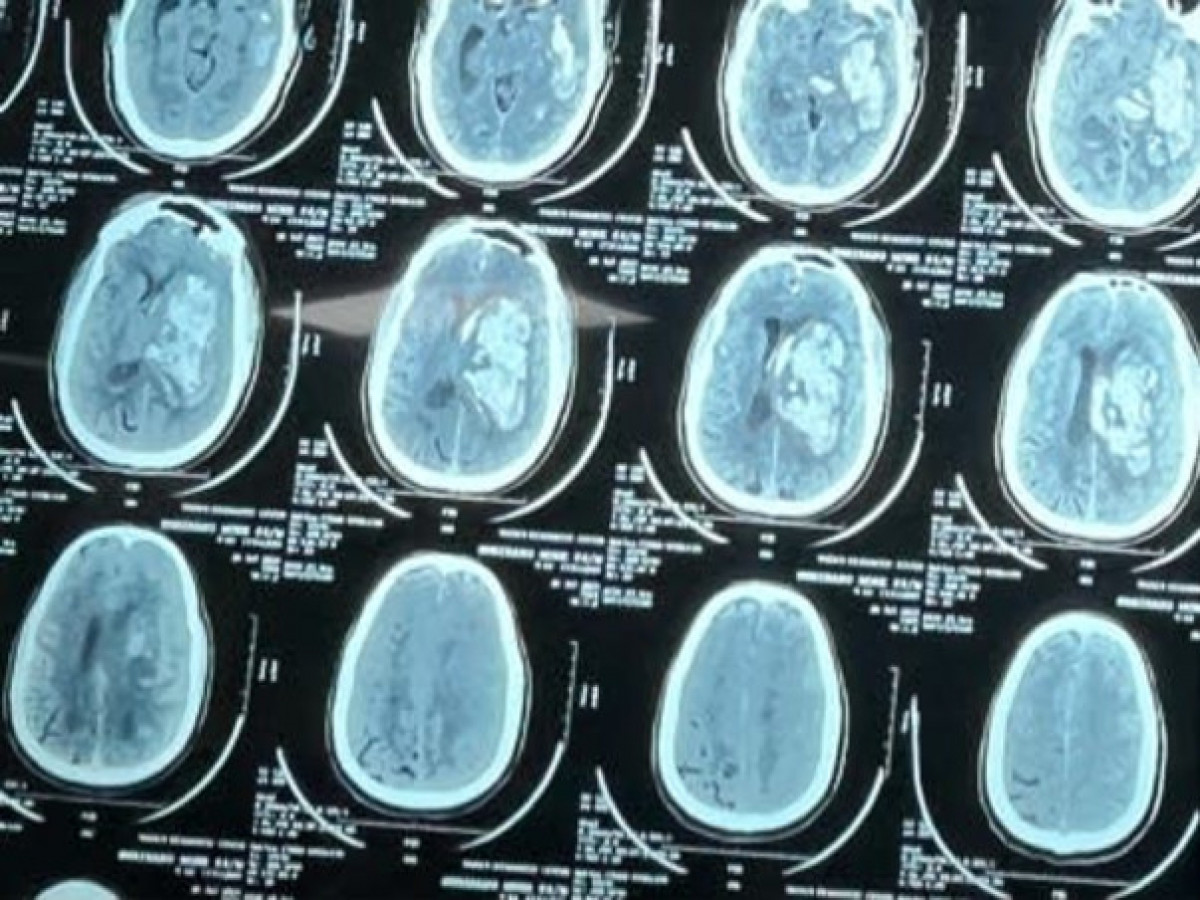

I’m struggling with Brain Stroke, help me

A few days ago, I suffered a brain stroke, and doctors have advised immediate surgery, as medicines can no longer help.